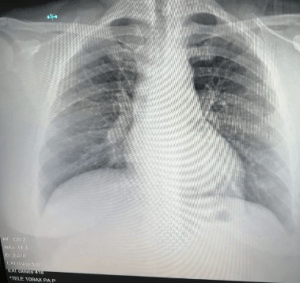

Bronconeumonía

Es la inflamación de los bronquiolos finos y sacos alveolares de los pulmones, producida generalmente por virus y bacterias. Los bronquiolos son los pequeños conductos que hay dentro de los pulmones.

Neumonía

Es una infección del pulmón que puede ser causada por múltiples microorganismos (bacterias, virus y hongos). Las neumonías se clasifican según se adquieren en el día a día de una persona (neumonía adquirida en la comunidad) o en un centro sanitario (neumonía hospitalaria).

Las infecciones de los pulmones, denominadas neumonías, son más graves, pero menos comunes

A causa de estos padecimientos, algunos pacientes necesitan rehabilitación pulmonar y broncodilatadores, medicina que ayuda a mantener abiertas las vías respiratorias en el pulmón, haciendo más fácil la entrada y salida de aire